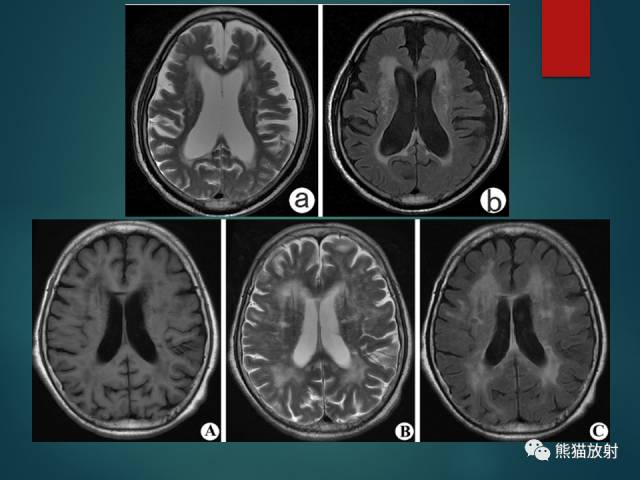

- 腔隙性脑梗死(LACI):颅内小动脉及穿支动脉狭窄或痉挛;T2-FLAIR呈高信号;DWI急性期弥散受限;基底节、脑干及丘脑多见。

- 血管周围间隙(PVS):与软脑膜下腔相连;分为基底节型、大脑半球型及脑干型;与脑脊液信号相同。